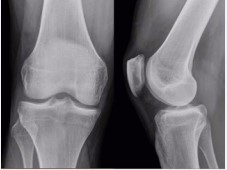

A 44 year old patient, male suffering from rheumatoid arthritis, complaining pain and clamping of the right knee for 5 years during the daily routine activities, with no associated trauma. The patient presents with a history of physiotherapy treatment and two arthroscopic procedures, with no improvement of symptoms. Radiographic examination revealed an image consistent with an intra-articular loose body in the medial compartment, in the topography of the posterior horn of the meniscus (Figure 1). The Magnetic Resonance Imaging (MRI) enabled the identification of bone tissue internal to the posterior horn of the medial meniscus (Figure 2). The surgical treatment was performed by arthroscopy via inter condylar access through the anterolateral and anteromedial portals (Figure 3) to position the optics and visualization of the posterior compartment (Figure 4). We identified the mensicalossicle adjacent to the posterior horn of the medial meniscus (Figure 5) and performed its removal utilizing basket forceps associated with economic resection of the posterior horn of the meniscus, due to the intimate anatomic relation between the two structures (Figures 6,7). The material was subjected to histopathological analysis, which identified fragments of meniscus containing hyaline alterations and metaplastic ossification, apart from a degenerative process, fibrosis, and foci of neovascularization (Figure 8). The patient evolved satisfactorily, with complete recovery of the range of motion and absence of joint locking symptoms, being that his last clinical evaluation was done with 3 months of postoperative. The last X-ray showed the absence of the bone body on the posterior compartment of the knee (Figure 9).

Figure 1: x-rays of the knee showing the bone body in the posterior region of the medial compartment.

Figure 9: Post-operative x-rays of the knee showing the absence of the bone body in the posterior region of the medial compartment.